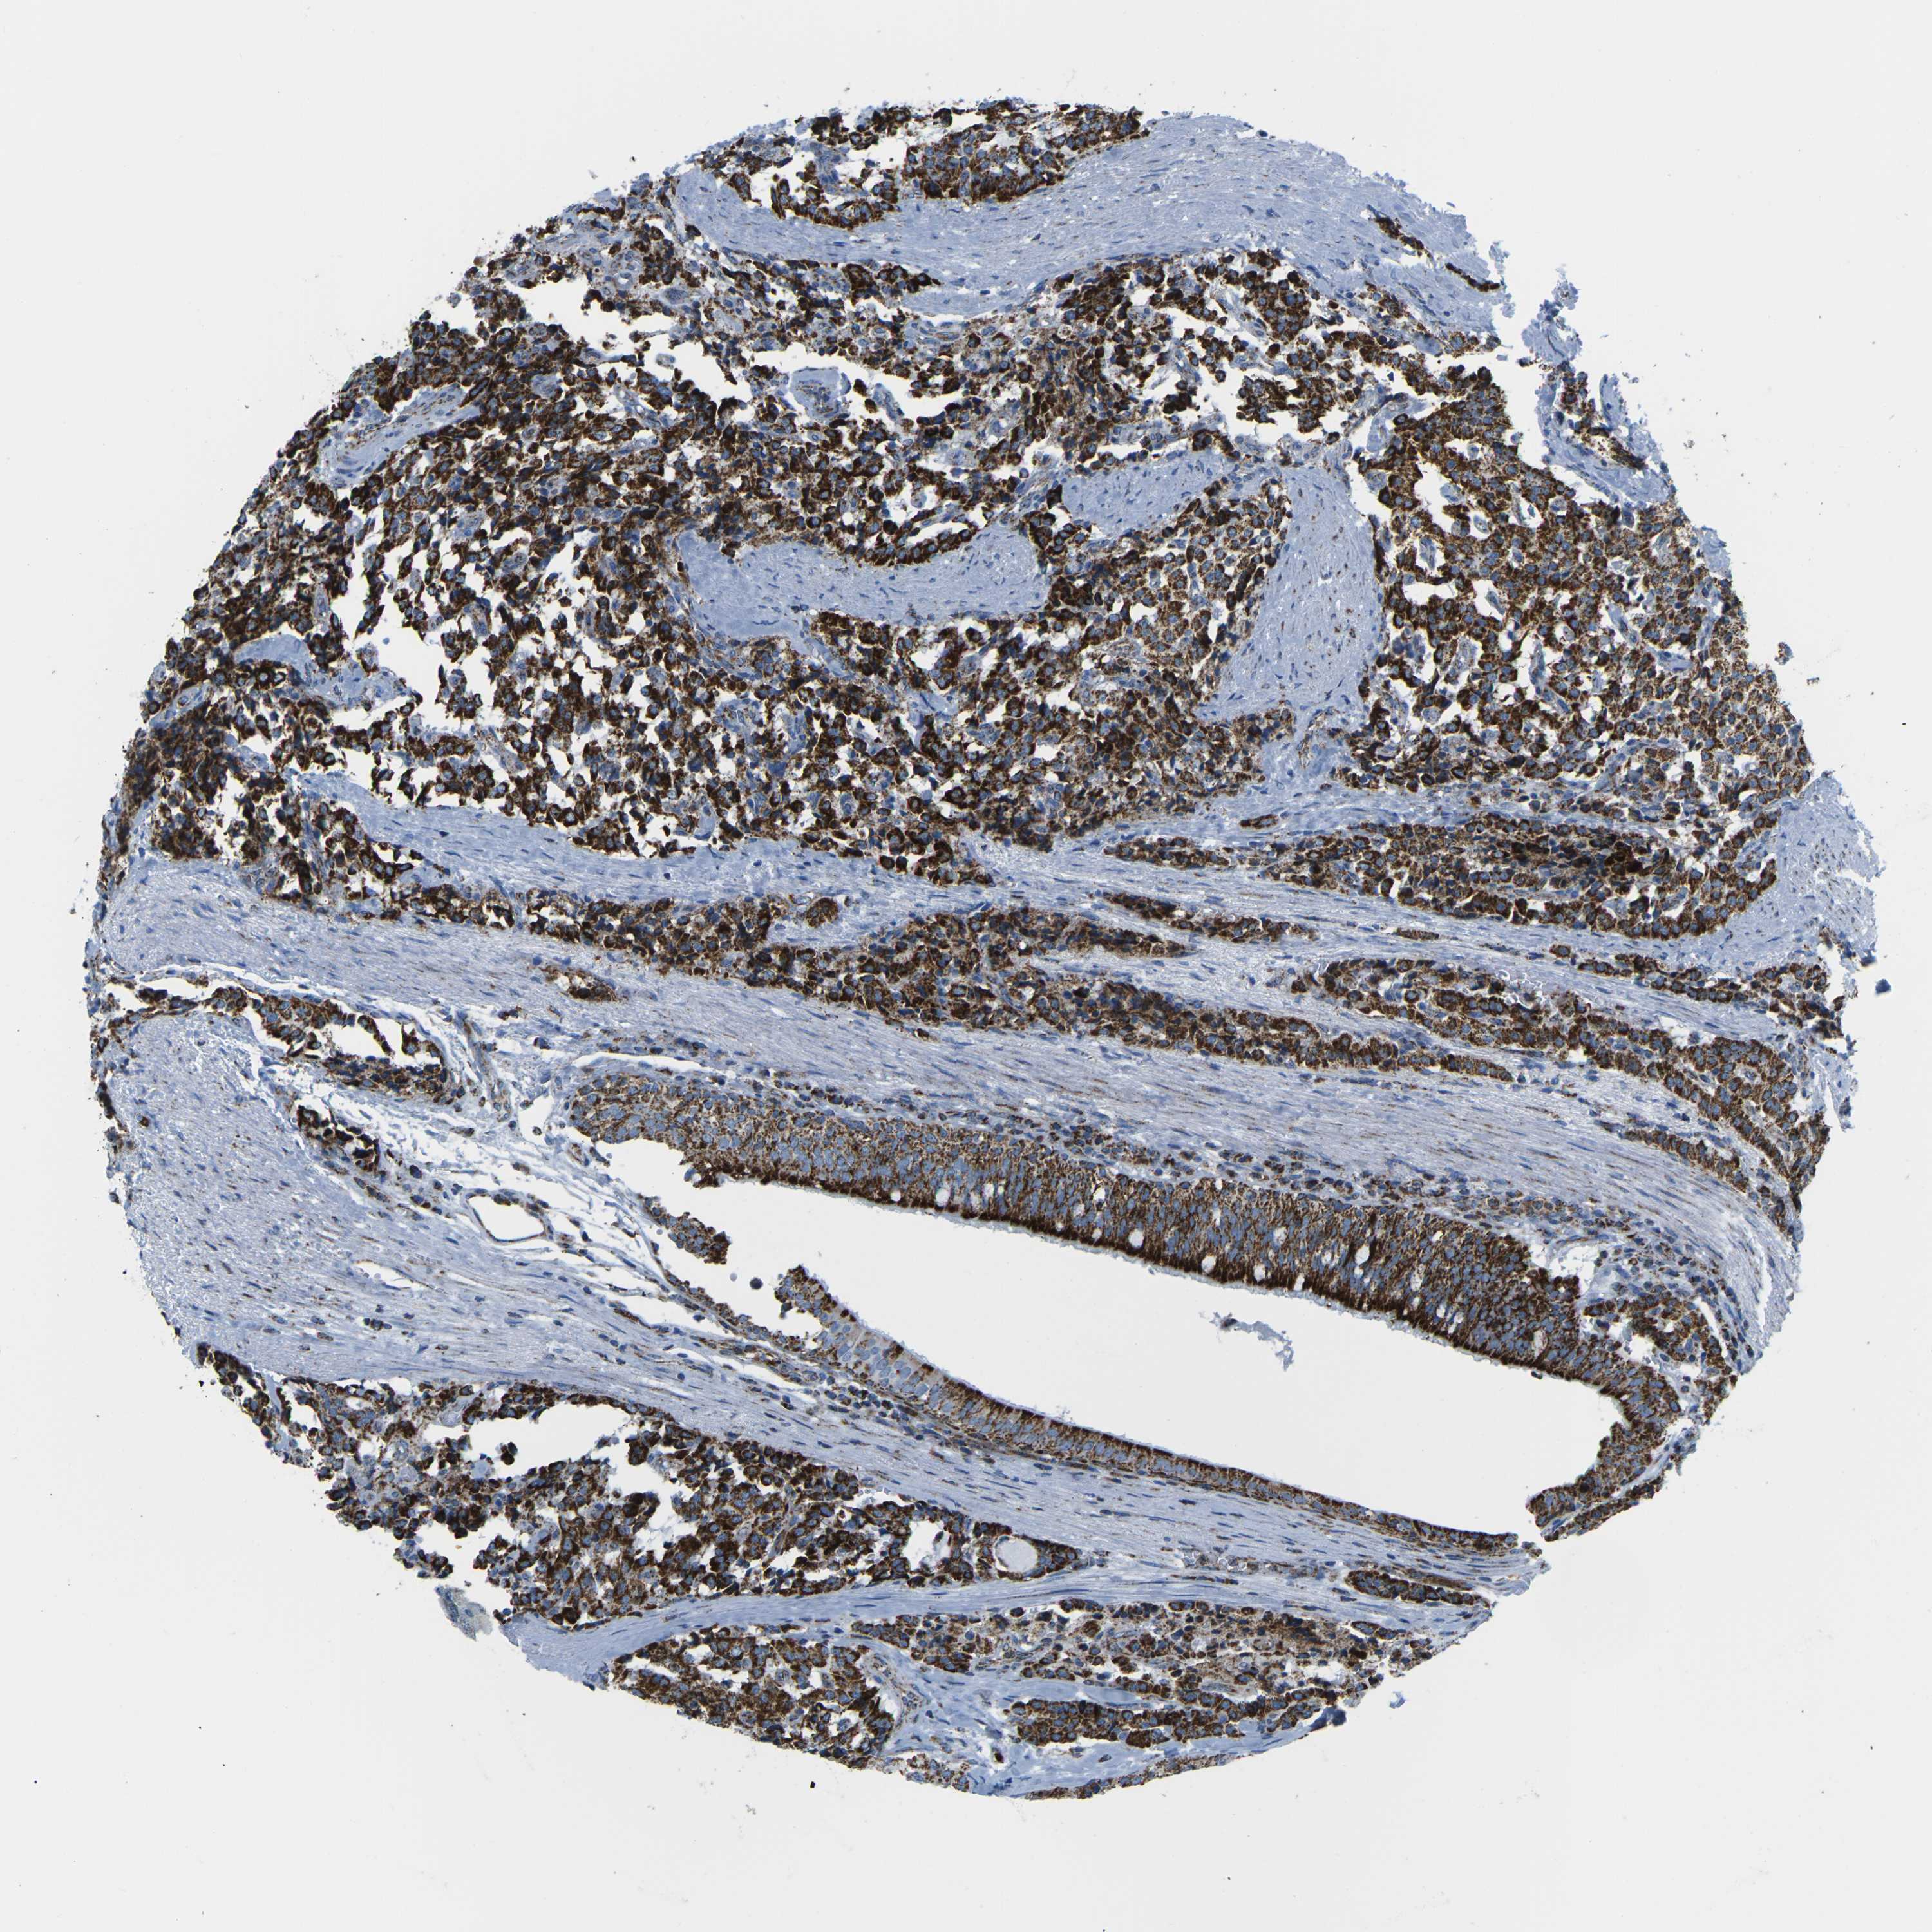

COX6C